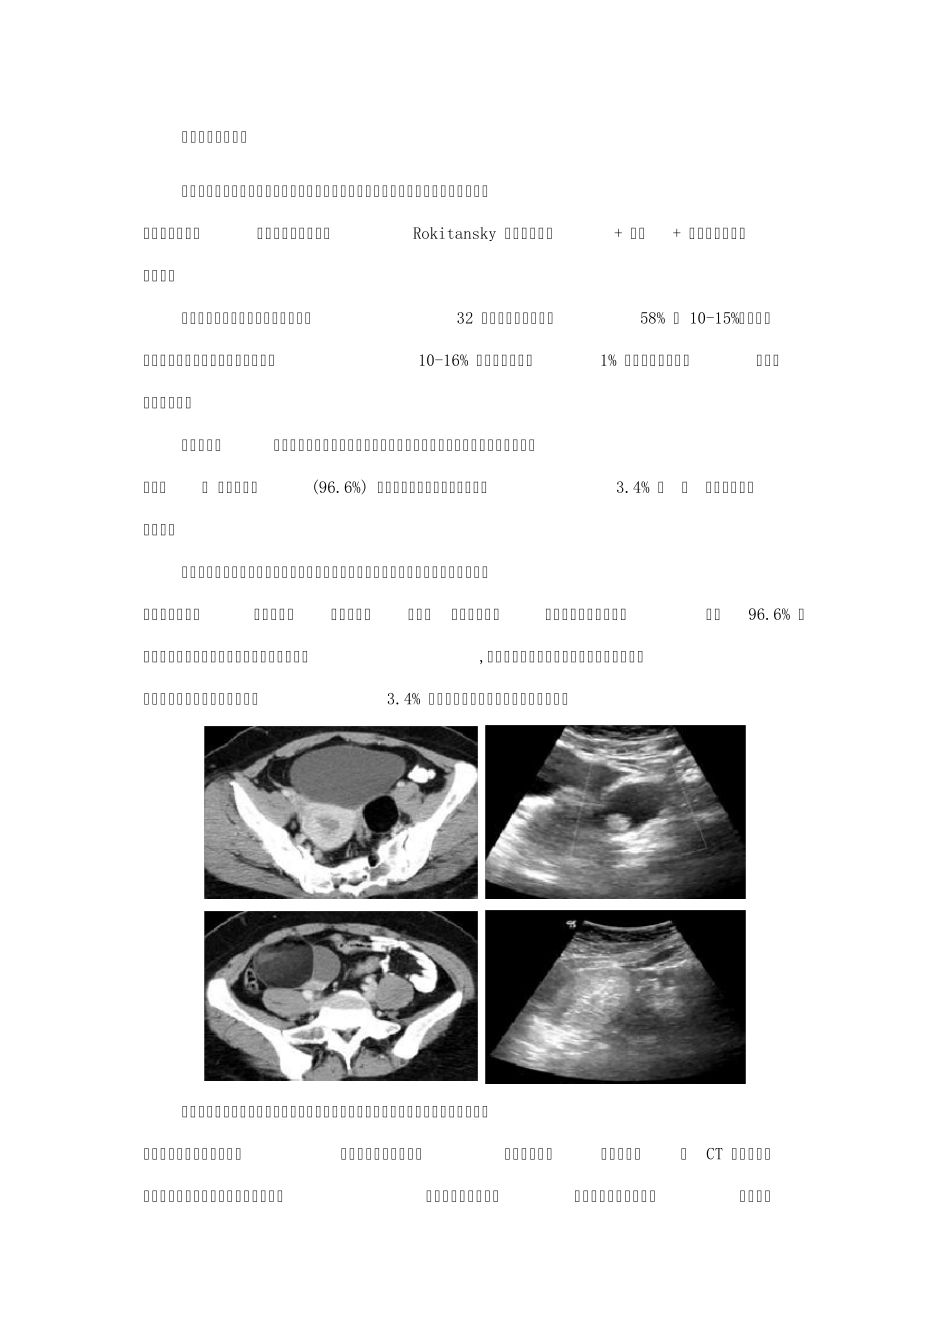

中国医学科学院协和医科大学 肿瘤医院肿瘤影像诊断科 戴景蕊 写在课前的话 卵巢肿瘤居生殖系肿瘤第二位,生殖细胞肿瘤占卵巢肿瘤20%, 因此关注卵巢生殖细胞肿瘤十分重要,而CT 是协助诊断的十分重要的参考资料。为提高对卵巢生殖细胞肿瘤CT诊断的认识,本课件从卵巢生殖细胞肿瘤的病理分类、临床特点、主要表现等方面做了介绍,重点对成熟性畸胎瘤、不成熟性畸胎瘤、无性细胞瘤等的CT 征象进行了详细介绍,旨在促进临床工作中对该病CT 诊断的认识。 一、卵巢生殖细胞肿瘤的相关介绍 卵巢肿瘤在病理学上可分为以下七类: 上皮间质肿瘤、性索间质肿瘤、生殖细胞肿瘤 、混合成份肿瘤、组织来源未定肿瘤、转移瘤、非特殊间叶组织肿瘤。从发病特点来看,上皮间质肿瘤占 65 ~ 75 %,性索间质肿瘤占 6 ~ 8 %,转移瘤占 5 ~ 10 %,而 生殖细胞肿瘤 约占 20 %,居于第三位。 生殖细胞肿瘤占卵巢肿瘤的( )。 A. 20% B. 65~ 75% C. 6~ 8% D. 5~ 10% 正确答案:A 解析:生殖细胞肿瘤约占20%。 其中卵巢生殖细胞肿瘤在病理上分为:原始生殖细胞肿瘤、两胚层或三胚层畸胎瘤、单胚层与皮样囊肿相关成人型。原始生殖细胞肿瘤又可以分为无性细胞瘤、胚胎性癌、卵黄囊瘤(内胚窦瘤)、非妊娠性绒毛膜癌、混合性生殖细胞瘤、多胚瘤。两胚层或三胚层的畸胎瘤有成熟型畸胎瘤、皮样囊肿和未成熟畸胎瘤。单胚层的与皮样囊肿相关成人型畸胎瘤常见的有甲状腺肿、类癌、原始神经外胚层肿瘤。临床上最多见的是成熟型畸胎瘤,其次是无性细胞瘤,还有胚胎癌、混合生殖细胞瘤,其他的肿瘤非常少见。 卵巢生殖细胞肿瘤从病理上还可以分为良性和恶性。良性肿瘤包括成熟畸胎瘤、皮样囊肿、甲状腺囊肿。恶性肿瘤有不成熟畸胎瘤、无性细胞瘤、胚胎癌、卵黄囊瘤、绒癌和混合生殖细胞肿瘤。良性肿瘤里最常见的是成熟畸胎瘤、皮样囊肿;恶性肿瘤里不成熟畸胎瘤和无性细胞瘤比较多见,其次是混合生殖细胞瘤,其他的肿瘤都比较罕见。 临床特点:卵巢肿瘤居生殖系肿瘤第二位,卵巢癌死亡率居妇科肿瘤首位,生殖细胞肿瘤占卵巢肿瘤 20% ,以成熟畸胎瘤 - 皮样囊肿多见,占卵巢良性肿瘤 50% 以上。 卵巢生殖细胞肿瘤的治疗原则多采用经腹手术的治疗。此外近年来,对于良性病灶也有腹腔镜切除手术的方法。 生殖细胞肿瘤的主要表现,从瘤体本身来讲主要是表现为囊实性的、混合性的或是实性肿块,诊断生殖细胞肿瘤最大的...